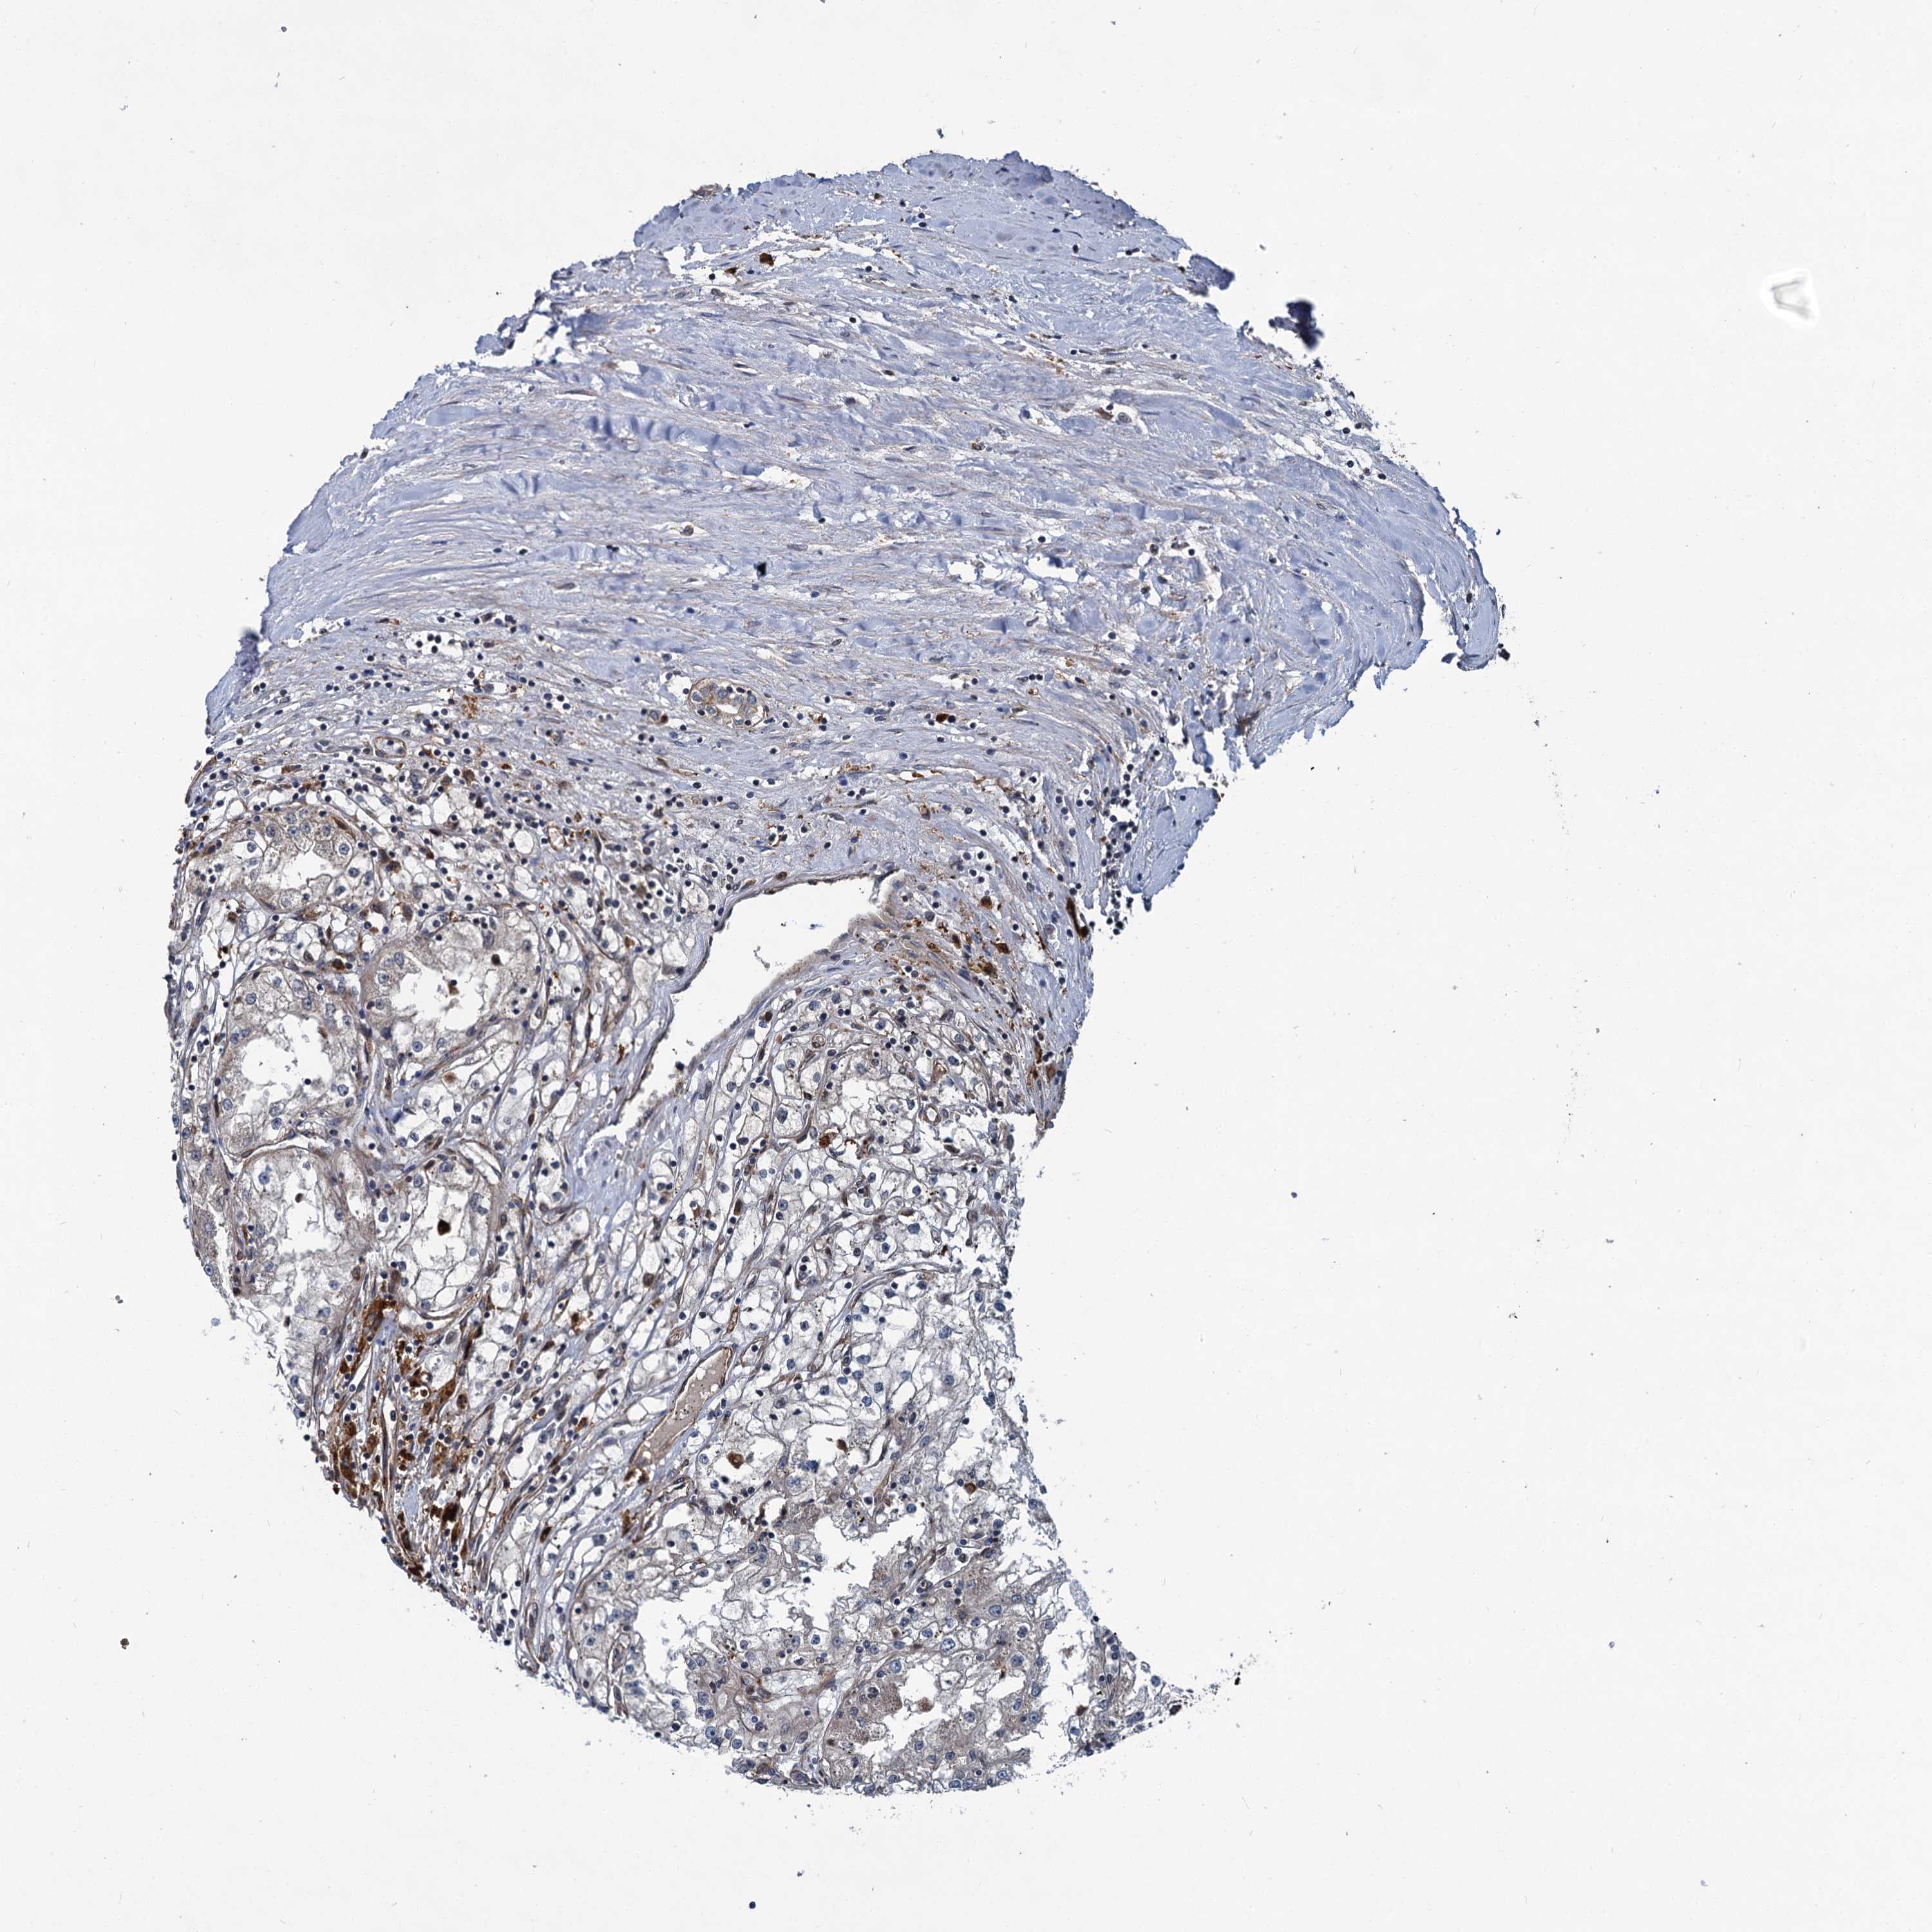

KIDNEY RENAL CLEAR CELL CARCINOMA (TCGA) - Interactive survival scatter ploti

The Survival Scatter plot shows the clinical status (i.e. dead or alive) for all individuals in the patient cohort, based on the same data that underlies the corresponding Kaplan-Meier plots. Patients that are alive at last time for follow-up are shown in blue and patients who have died during the study are shown in red.

The x-axis shows the expression levels (FPKM) of the investigated gene in the tumor tissue at the time of diagnosis. The y-axis shows the follow-up time after diagnosis (years). Both axes are complimented with kernel density curves demonstrating the data density over the axes. The top density plot shows the expression levels (FPKM) distribution among dead (red) and alive patients (blue). The right density plot shows the data density of the survived years of dead patients with high and low expression levels respectively, stratified using the cutoff indicated by the vertical dashed line through the Survival Scatter plot. This cutoff is automatically defined based on the FPKM cutoff that minimizes the p-score. The cutoff can be changed by dragging the vertical line or by entering a cutoff value in the square labeled "Current cut-off".

Under the Survival Scatter plot the p-score landscape (black curve; left axis) is shown together with dead median separation (red curve; right axis). Dead median separation is the difference in median mRNA expression between patients who have died with high and low expression, respectively. It is calculated as follows: median FPKM expression of dead patients with high expression - median FPKM expression of dead patients with low expression. This is intended to aid the user in visually exploring custom cutoffs and the associated p-scores and dead median separation.

Individual patient data is displayed and can be filtered by clicking on one or more of the category buttons on the top of the page. Categories describing expression level and patient information include: high, low, alive, dead, female, male and tumor stages. The scale of the x-axis can be toggled between linear and log-scale by clicking on the "x log" button. Mouse-over function shows TCGA ID, patient information and mRNA expression (FPKM) for each patient.

& Survival analysisi

Kaplan-Meier plots summarize results from analysis of correlation between mRNA expression level and patient survival. Patients were divided based on level of expression into one of the two groups "low" (under cut off) or "high" (over cut off). X-axis shows time for survival (years) and y-axis shows the probability of survival, where 1.0 corresponds to 100 percent.

ZFYVE19 is validated prognostic, high expression is favorable in Kidney Renal Clear Cell Carcinoma (TCGA)

Best expression cut offi

Based on the FPKM value of each gene, patients were classified into two groups and association between prognosis (survival) and gene expression (FPKM) was examined. The best expression cut-off refers the FPKM value that yields maximal difference with regard to survival between the two groups at the lowest log-rank P-value. Best expression cut-off was selected based on survival analysis .

When clicking on this number, the vertical dashed line indicating cut-off, the interactive survival plot, and the Kaplan-Meier curve will be adjusted to show results based on the best expression cut-off.

: 13.46

TCGA RNA samplesi

RNA-seq data is reported as average FPKM (number Fragments Per Kilobase of exon per Million reads), generated by the The Cancer Genome Atlas (TCGA) .

Normal distribution across the dataset is visualized with box plots, shown as median and 25th and 75th percentiles. Points are displayed as outliers if they are above or below 1.5 times the interquartile range. FPKM values of the individual samples are presented next to the box plot.

Average pTPM 11.7

Number of samples 521